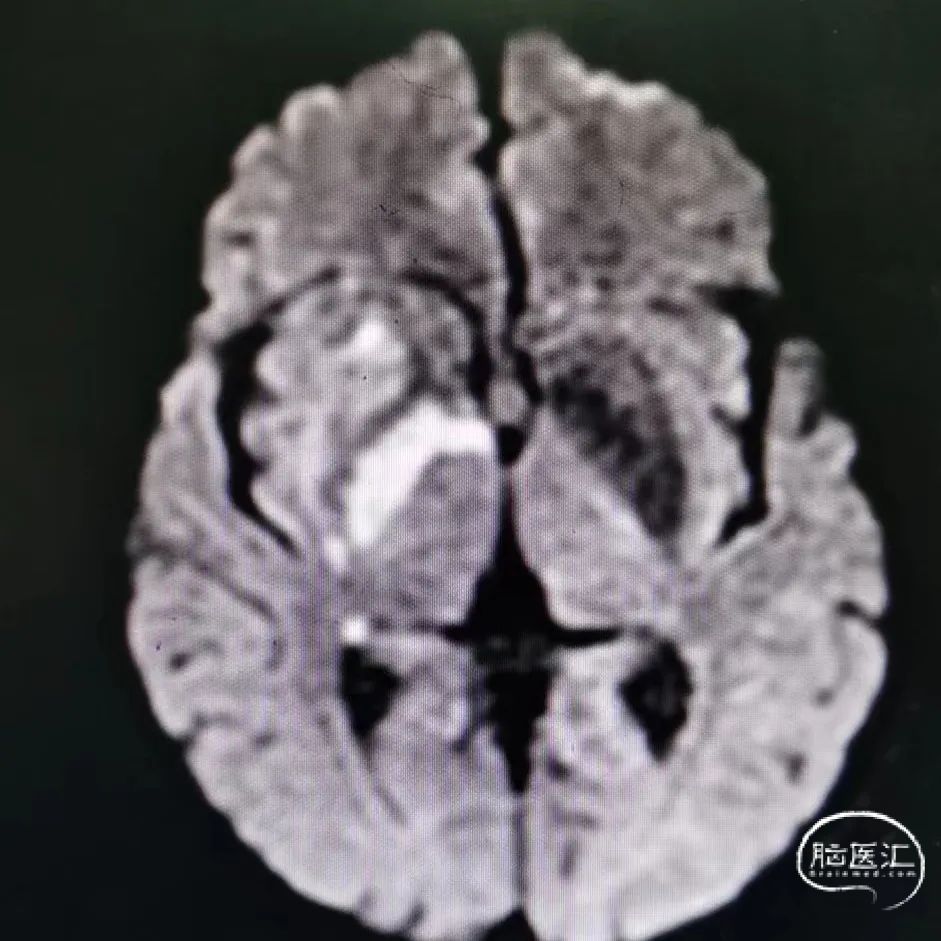

术后影像:

术后第1天,NIHSS 0分。